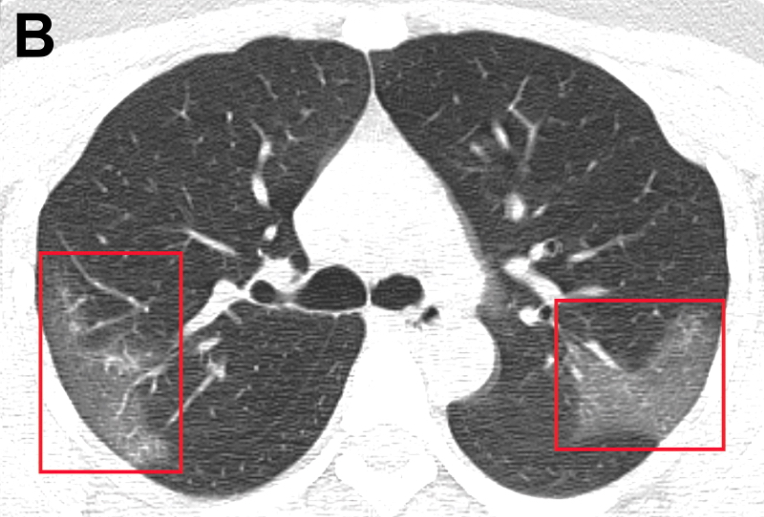

N Engl J Med, 28 de febrero de 2020Durante los primeros 2 meses del brote, el Covid-19 se propagó rápidamente por toda China y causó diversos grados de enfermedad. Los pacientes a menudo se presentaron sin fiebre, y muchos no tenían hallazgos radiológicos anormales.